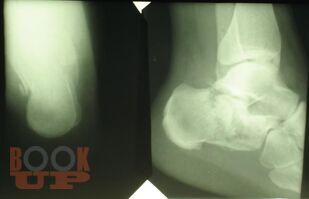

Учебное пособие содержит необходимую информацию для врачей по вопросам оказания специализированной помощи пострадавшим с тяжелой травмой костей нижних конечностей. Подробно освещены вопросы патогенеза шока как основной причины развития травматической болезни, а также тактики оказания специализированной и высоко квалифицированной помощи пострадавшим с тяжелыми монолокальными и множественными переломами костей нижних конечностей в зависимости от периода развития травматической болезни. Особое внимание уделено профилактике и лечению ранних осложнений тяжелых переломов костей нижних конечностей – синдрому жировой эмболии, тромбоэмболическим осложнениям. В пособии обобщен более чем 30- летний опыт лечения пациентов с тяжелой травмой костей нижних конечностей.